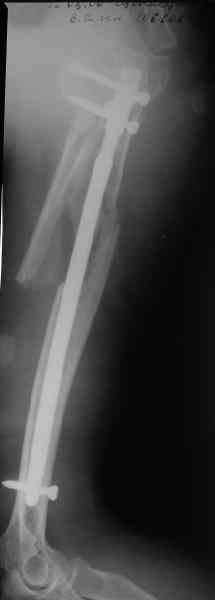

Здесь нет необходимости в серкляже. Вмешиваться на промежуточных

отломках приходится, если есть угроза перфорации кожи, или

промежуточный отломок попал в фасцию, как пуговица в петлю. В

приложении сегментарный оскольчатый перелом плеча в проксимальном

отделе, фиксированный больщеберцовым стержнем. Как видите, обошлось

без серкляжа. Функция полная.